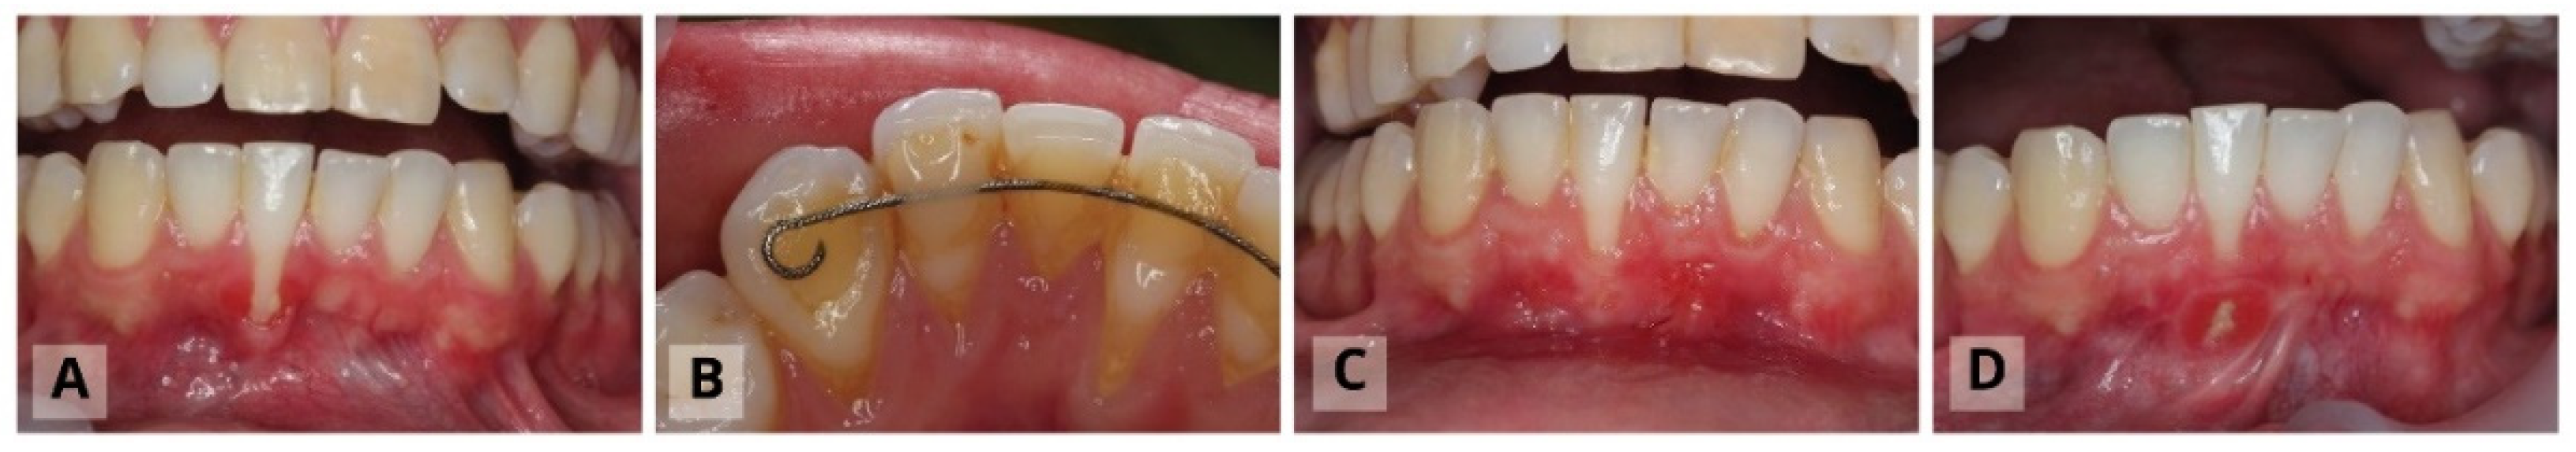

The Surgical Procedure: Modified Tunnel Double Papilla Procedure for Root Coverage